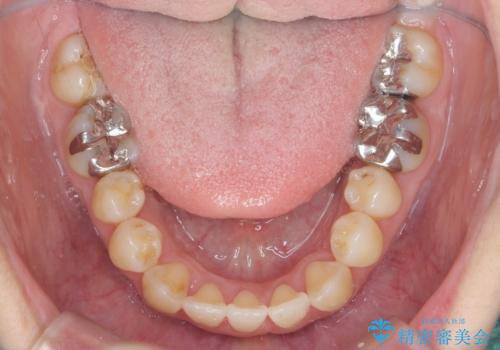

前歯のがたつき すれ違い咬合のマウスピース矯正治療

- 前歯のがたつきや歯の角度、矯正治療を希望され来院されました。

仕事の都合で、ワイヤー矯正を行うことが難しくマウスピース矯正であれば可能、という希望でした。

下顎が前にある咬合関係を可及的に咬合移動で改善し、IPR、下顎3前歯の仕上げで行うマウスピース矯正を計画します。

他院では、「マウスピース矯正では治らない。」と言われ当院に相談に見えましたが、マウスピースで達成できるゴールを模索することで矯正治療を行えることがあります。